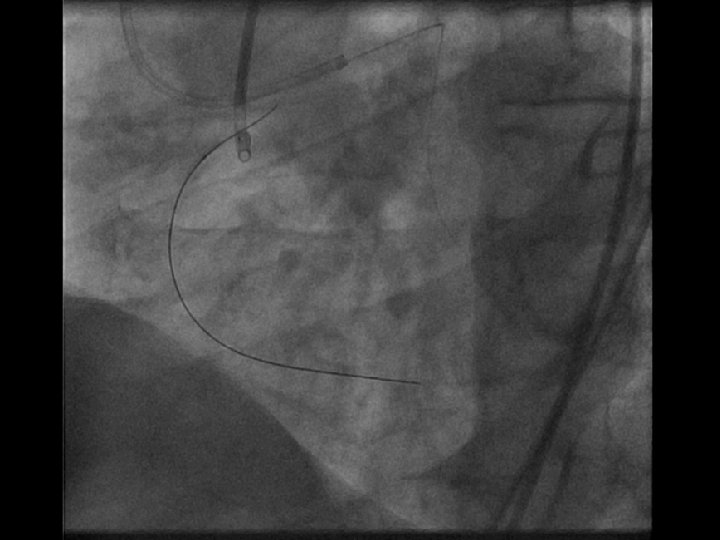

Direct Retrograde Crossing Via LAD Septal route Retro wire: Fielder FC® over the 2.

Direct Retrograde Crossing Via LAD Septal route Retro wire: Fielder FC® over the 2. 5 mm OTW Balloon